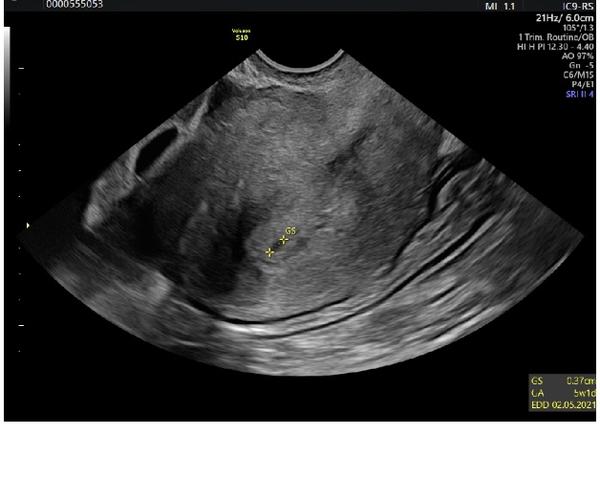

na té poslední fotce náznak gestačního váčku, ale pokud nevidí víc doktoři, tak těžko laici na foru :( Přeji hodně štěstí

Tak já nevím... 4. fotka vypadá jako vaječník a 5. jako váček (podle zobrazení týdne) 😁